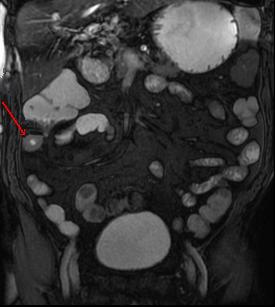

| Maladie de Crohn , Image

epaissisement de la paroi de ileon avec aspect stenosant de

la lumen ( fleche rouge ) . Image IRM en

coupe coronal |

| Maladie de Crohn :

Aspect epaissisement de la paroi de ileon avec image

en beigne " combs sign " c'est image de spiculation des vaisseaux

mesenterique droit . Image IRM T2 W en coupe coronal |